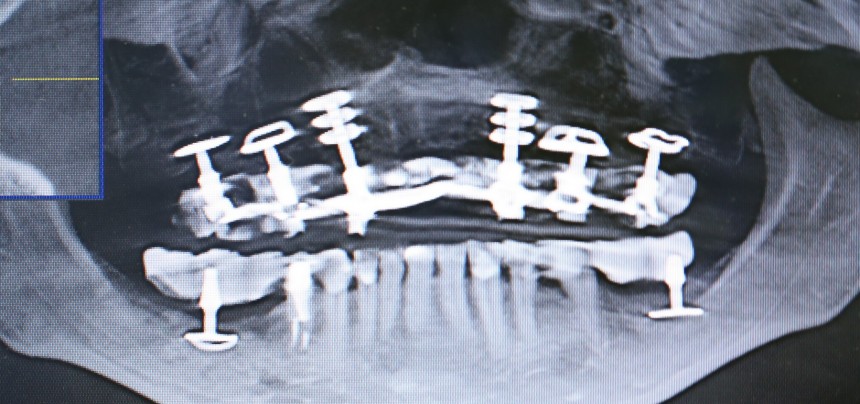

А теперь посмотрите снимок этого пациента:

Как вы считаете, что будет травматичнее и опаснее: установка шести имплантов такой формы или два простых синуслифтинга и шесть обычных имплантов?

К слову сказать, базальные импланты не интегрируются, а удерживаются, исключительно, за счет своей формы:

А это значит, что длительная функциональная нагрузка в таком объеме просто будет их медленно расшатывать. Особенно, если учесть, что их нагружают почти сразу после установки. И весьма большой протетической конструкцией.

И вот, у этой пациентки все импланты, а их, ни много, ни мало, восемь штук, подвижны:

Мы вынуждены их удалить. И теперь представьте, как будет проходить такое удаление и с каким дефицитом костной ткани мы, в итоге столкнемся. Что вообще делать дальше? Девушка плачет.